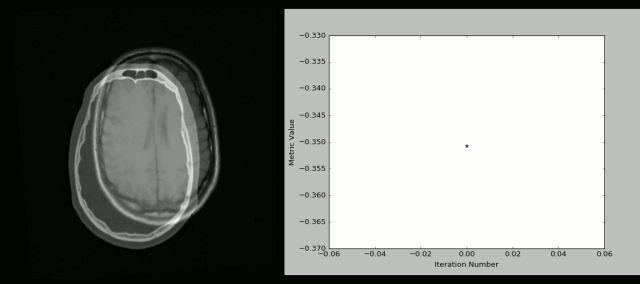

下面就是用SimpleITK和Python创建的可视化的CT/MR图:

官方地址:https://itk.org/

学习资料:http://insightsoftwareconsortium.github.io/SimpleITK-Notebooks/